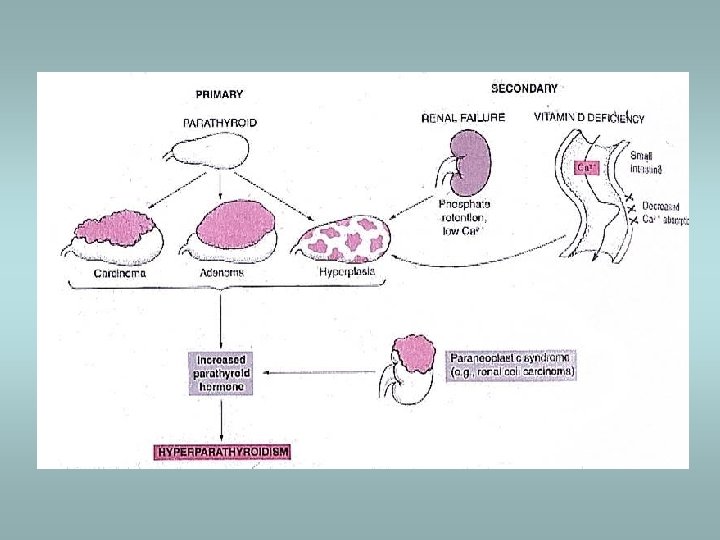

Parathyroid gland Primary hyperparathyroidism ü Hypersecretion of parathormone ü Caused by adenoma (80%), hyperplasia (15%), carcinoma (5%) ü Bone resorption, hypercalcemia – osteoporosis, muscle weaknes, nephrolithiasis, ulcers, pancreatitis, headache, depression Secondary hyperparathyroidism ü In patients with renal failure ü Compensatory hypersecretion of parathormone (reaction to phosphate retention and hypocalcemia)

Parathyroid gland - tumors Adenoma ü Solitary, encapsulated – compression of adjacent gland ü No stromal fat ü Composed predominatly of chief cells ü Part of MEN I, MEN II Carcinoma ü Rare ü Invasion, metastases Hyperplasia ü All glands ü Fat cells interspersed